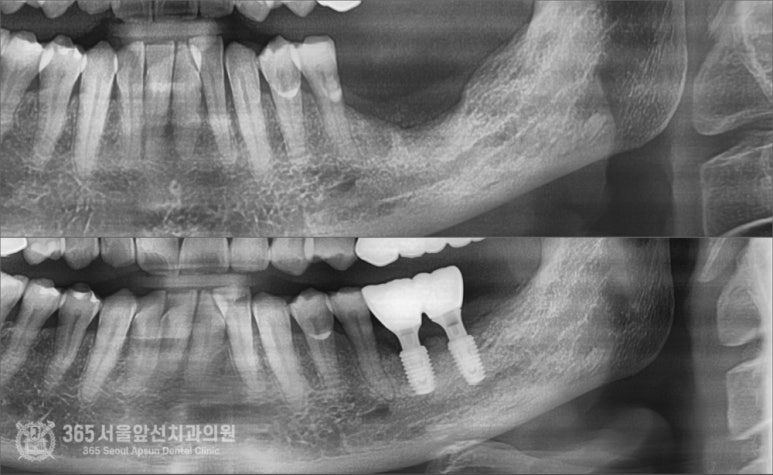

촬영일시: 2024.07.07. 제거하고 대략 2개월 정도 지나고 엑스레이입니다. 뼈가 움푹 파여서 이 상태로는 임플란트 식립이 어려운 상황입니다. 촬영일시: 2024.08.10. 골이식과 동시에 임플란트를 식립하였고 사진의 노란색 부위만큼이 골이식이 들어간 부위입니다. 이 환자분의 증례에서 시행된 골이식술은 수직골증강술이라는 매우 고난이도 술식입니다. 하지만 숙련된 의료진과 함께라면 걱정안하셔도 되겠습니다 ㅎㅎ 촬영일시: 2024.10.10. 약 5개월 정도 지난 후 잇몸을 열어서 이식된 골이 잘형성되었는지 확인함과 동시에 임플란트도 뼈와 잘결합되었는지 확인합니다. 다행히 뼈 형성도 좋고, 임플란트도 단단하게 잘 붙었습니다 ㅎㅎ

촬영일시: 2024.05.11. / 2024.10.20. 임플란트 보철물을 완성한 후 엑스레이 사진입니다. 난이도가 높은 재수술 케이스임에도 성공적으로 마무리되었습니다. 오늘은 주안역 임플란트 재수술 증례를 소개해드렸습니다. 아무리 어려운 수술이더라도 다 방법은 있기에 너무 걱정은 안하셔도 괜찮을 것 같습니다 ㅎㅎ 앞으로도 좋은 증례로 찾아뵙겠습니다. 지금까지 365일 열린 가까운 서울대학교 치과병원을 지향하는 주안역치과 365서울앞선치과였습니다. 감사합니다. ※ 365서울앞선치과의원의 모든 포스팅은 각 진료과 의료진이 직접 작성합니다. 365서울앞선치과의원 블로그의 임상 케이스 게시물은 환자분께 의학적으로 정확하고 상세한 정보를 드리기 위해 각 진료과 의료진이 직접 작성하며, 모든 증례 사진은 본원 의료진이 직접 시술한 증례를 촬영한 것으로, 의료법 제23조, 제56조에 의거하며 환자분의 동의를 얻어 포스팅에 사용하였습니다. 또한 해당 케이스는 본 환자분의 치료 결과이며, 환자 상태에 따라 치료의 결과는 달라질 수 있습니다. |